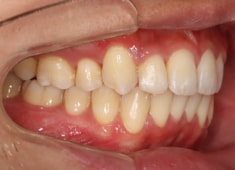

治療開始から24ヶ月後